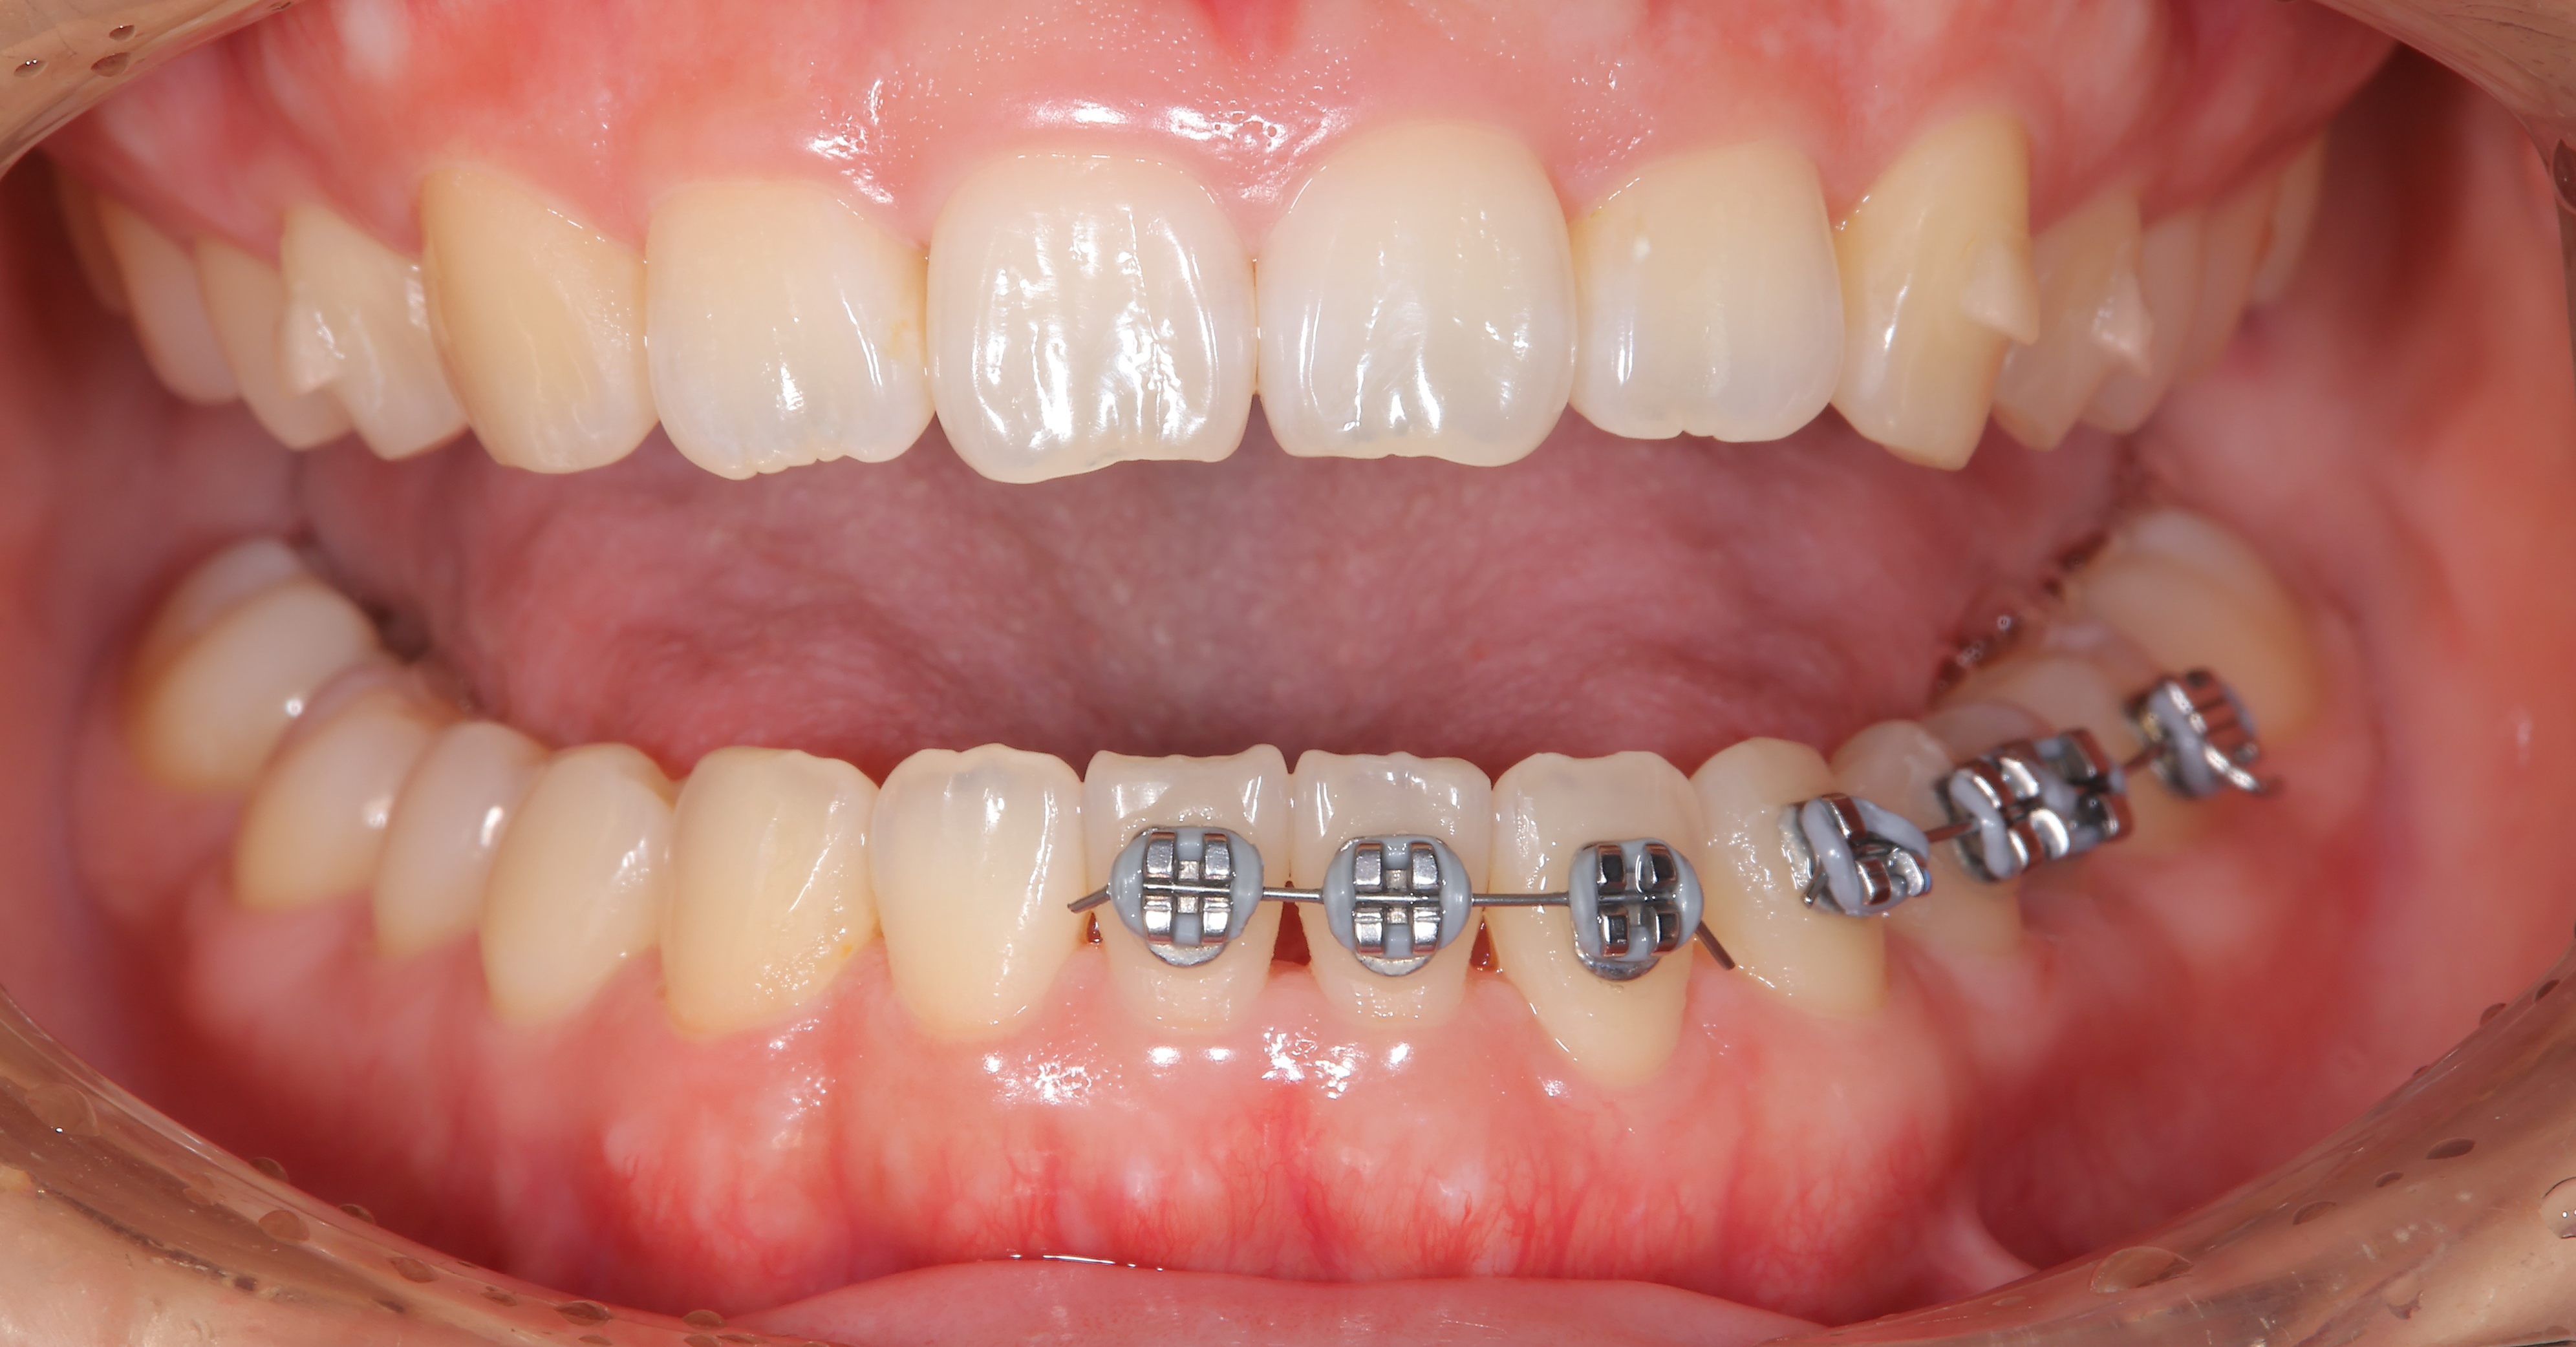

治療概要:矢印の歯は反対咬合(上の歯より下の歯の方が前に出ている)になっています。また、この方も過蓋咬合で下の前歯がほとんど見えません。

奥歯の噛み合わせはほとんど問題なく、マウスピース矯正を提案し矯正スタートしました。マウスピース矯正は食事中は外せたり、歯磨きもしっかりできるので良い治療法ですが、2番目の歯などあまり凹凸の少ない歯は動きが悪いことがあります。

行った治療

ほぼ他の歯が並んだ状態でも、やはりこの矢印の歯だけ動きが悪かったのと、左下の捻れた歯がなかなか治らなかったので、ワイヤーを部分的に使用させてもらいました。

下の写真が術前術後の比較です。下の前歯が見えるようになりました。上の前歯の傾きが変わるだけで口元の印象も変化します。